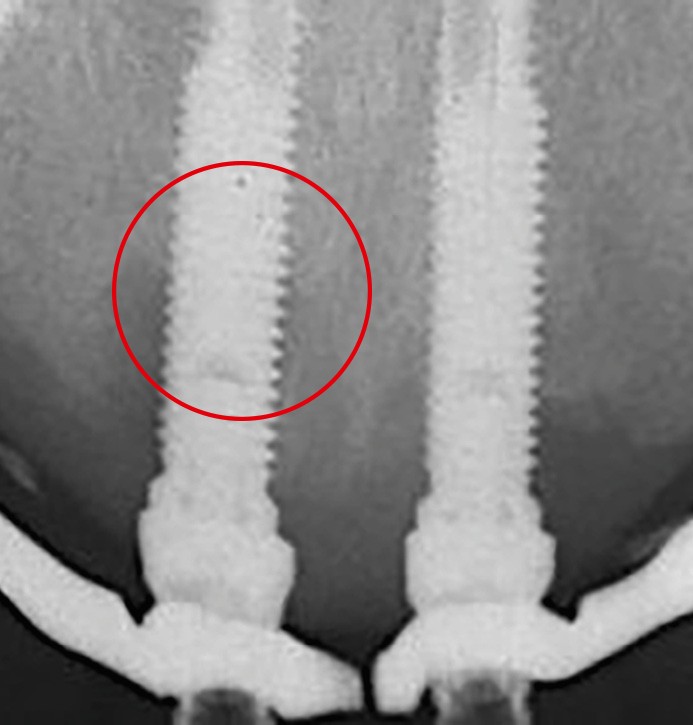

La péri-implantite

La plaque bactérienne (biofilm) pénètre et envahit les tissus muqueux autour des implants dentaires (fig. 3). S’installent une inflammation de la muqueuse péri-implantaire et la perte progressive et asynchrone du tissu osseux [4]. La péri-implantite survient au cours des premières années de mise en fonction de l’implant [4] et en l’absence de traitement, la maladie progresse (fig. 4) de manière non linéaire et rapide [4, 7].